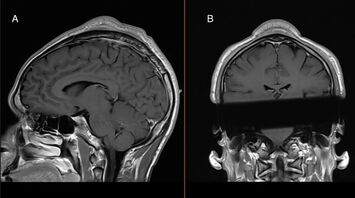

During surgery, the lump was successfully removed, alleviating the man's discomfort and enabling him to socialize mask-free without hiding under hats. Although this condition is informally known among breakers and on platforms like Reddit, where practitioners discuss bald spots and share protective tips such as using padded beanies, it's scarcely documented medically.